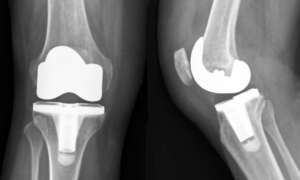

İlk adım, cerrahın dizin etrafındaki dokuları açarak eklem yüzeyine ulaşmasıdır. Genellikle, dizin ön kısmından küçük bir kesi yapılır. Bu kesiden girilerek, zarar görmüş kıkırdak ve kemikler temizlenir. Daha sonra, özel bir metal ve plastik bileşen yerleştirilir. Bu bileşen, eski eklemin yerini alacak şekilde dizin içinde sabitlenir.